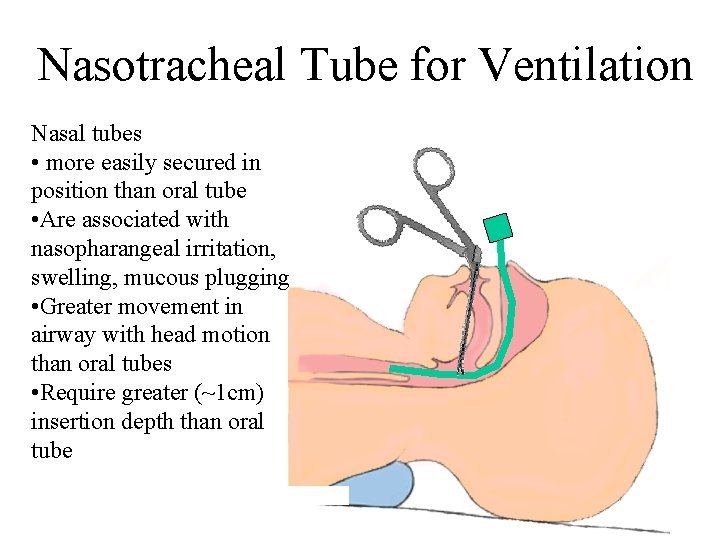

Nasotracheal Tube for Ventilation Nasal tubes • more easily secured in position than oral tube • Are associated with nasopharangeal irritation, swelling, mucous plugging • Greater movement in airway with head motion than oral tubes • Require greater (~1 cm) insertion depth than oral tube